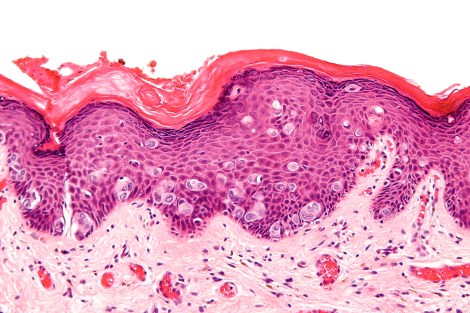

The word “pathology” is derived from the Greek words, “pathos-” meaning “experience” or “suffering” and “-logia” which translates as “the study of“. When people think of Pathology, most often they envision the subspecialty of Anatomic Pathology, in which a clinician or scientist uses histology to study a disease process. Histology, or the study of tissues, studies the microscopic anatomy of cells and tissues. The gold standard stain for observing the basic composition of a given tissue is the hematoxylin & eosin (H&E) stain. Hematoxylin stains the nuclei of cells blue, meanwhile eosin stains the cytoplasm and extracellular proteins like collagen pink.

- Distinct patterns of tumor formation. Some tumors can form unique arrangements within themselves, like whirling patterns or rosettes (see the header image for this blog as an example). Sometimes these patterns can also form around blood vessels, especially since actively growing tumors need considerable blood supply.

- Invasion. Tissues are divided into layers and nuclei, each of which usually show distinct boundaries between different cell types. When one cell type crosses that boundary into another, that can be indicative of malignancy (see image below).

In this image you can see a clear indication of an invasive cancer, in which you see large cells invading the epidermis of the skin of the breast. This is taken from a patient with Extramammary Paget’s Disease. Image borrowed from here.